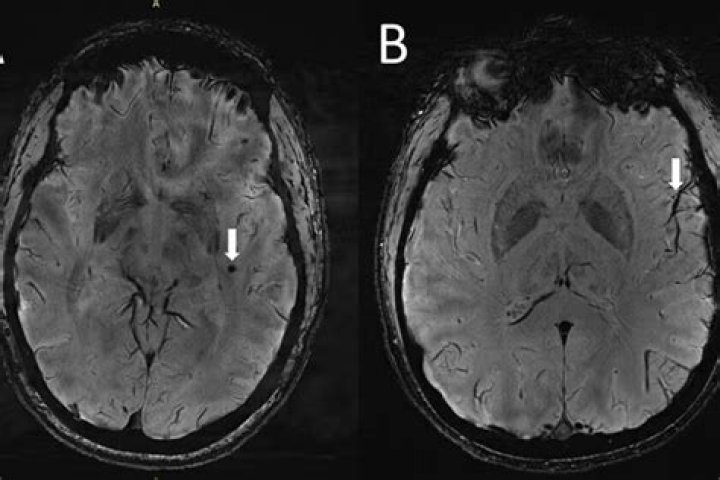

Will brain damage show on MRI?

Can an MRI show early signs of dementia?

NYU Langone study shows a new tool for analyzing tissue damage seen on MRI brain scans can accurately detect early signs of cognitive decline. A new tool for analyzing tissue damage seen on MRI brain scans can detect with more than 70 percent accuracy early signs of cognitive decline, new research shows.

Can white spots on brain be harmless?

White matter lesions are among the most common incidental findings—which means the lesions have no clinical significance—on brain scans of people of any age. They may also reflect a mixture of inflammation, swelling, and damage to the myelin.